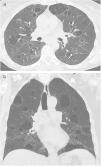

Langerhans cell histiocytosis (LCH)LCH is a rare tobacco-related interstitial lung disease diagnosed in young adults with a current or previous history of smoking. Components of tobacco smoke are thought to activate pulmonary Langerhans cells, which, along with other inflammatory cells, accumulate to form peribronchial infiltrates and granulomas that result in stellate nodules. These nodules may show cavities that correspond to bronchiolar dilatation. In the most advanced stages, peribronchial fibrosis pulls and dilates the contiguous air spaces.14 The most common symptoms are dyspnoea and cough, but there are often no respiratory symptoms. Some patients start with pneumothorax (15%), and a small percentage have systemic symptoms, pain secondary to bone involvement, cutaneous eruptions, or diabetes insipidus. Chest radiographs may reveal upper lobe nodules in the initial phases, and later reticular and cystic abnormalities, with preserved or increased lung volumes. On CT in the initial phases, peribronchiolar centrilobular nodules predominate, measuring 1−5mm, which are poorly defined or irregular, with bilateral and symmetrical distribution, predominantly in the upper and middle lung fields, with the costophrenic angles and the internal part of the middle lobe and the lingula preserved. As the disease progresses, cavitated nodules appear (Fig. 7) with thick walls and, later on, thin-walled cysts of different sizes, generally less than 1cm. However, they may coalesce in advanced stages, and large cysts with irregular or atypical (lobulated, branched, etc.) morphology are seen. (Fig. 8) Both pathologically and on CT, there is temporal heterogeneity, and cavitated nodules may coexist with thick- and thin-walled cysts.2,5,6,12 The hypothesised mechanism of cyst formation is dilatation of the bronchioles secondary to chronic inflammation with destruction of their walls.15 In the more advanced stages there is fibrotic scarring and peribronchiolar paracicatricial emphysema. The disease may return spontaneously or after smoking cessation in 25% of patients, stabilise in 50%, or progress to diffuse destructive cystic disease in 25% with respiratory failure, even after smoking cessation. Pulmonary hypertension is a complication associated with higher mortality and is usually more serious than that related to other causes, such as emphysema or pulmonary fibrosis.31 Its prevalence is high, around 40% in a recent series,32 so screening with echocardiography is indicated. In patients with long-standing disease and significant cystic involvement of the lungs, mimicking extensive emphysema, the existence of signs of pulmonary hypertension may guide us towards diagnosing LCH. It is not possible to determine with CT the subgroup of patients with LCH that will progress, so follow-up with respiratory function tests is important. Lung transplantation is an option in cases of advanced disease.

Langerhans cell histiocytosis. (A) The HRCT image centred on the upper lobes shows multiple subcentimetre nodules with irregular contours, some cavitated (white arrows) and also air-filled cystic images (black arrow). (B) The image reconstruction in the coronal plane highlights the predominant distribution in the upper lung fields, with preservation of the lung bases.